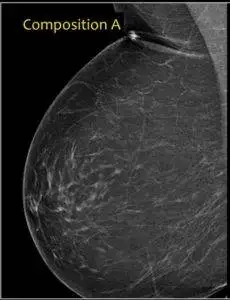

Cat. A: Predominantly Fatty.

Breasts that fall in this category are known to be almost all fatty. Since fatty tissues are not dense, the mammogram of category A breasts appears uniformly grey with no observable areas of fibroglandular densities. 1 out of every 10 women has breasts that fall in this category. That is, 10% of women have such breasts.

There was no way I could discuss dense breasts specifically, without showing you images. Therefore I obtained all these images from “Radiology Assistant”, of the Netherlands and I am grateful.

They were very thorough on this subject and included an exciting approach I liked, in distinguishing the categories mentioned above.

Category. A: Less than 25% Fibroglandular.